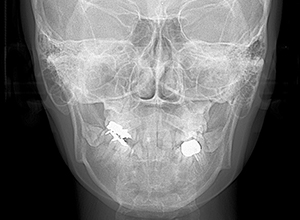

X-Ray

X-Ray所見

セファロ所見 下顎骨体部は小さくないものの下顎枝は短く、下顎頭は後方に位置付き中顔面高は高いため、下顎はクロックワイズローテーションしており、前後的にはII級の骨格形態を示していた。

パノラマ所見 上下顎両側第三大臼歯は埋伏していた。下顎右側大臼歯から犬歯まで近心傾斜し、左側においては左下5を境に大臼歯は近心傾斜、近心の歯は遠心方向へ傾斜が認められた。